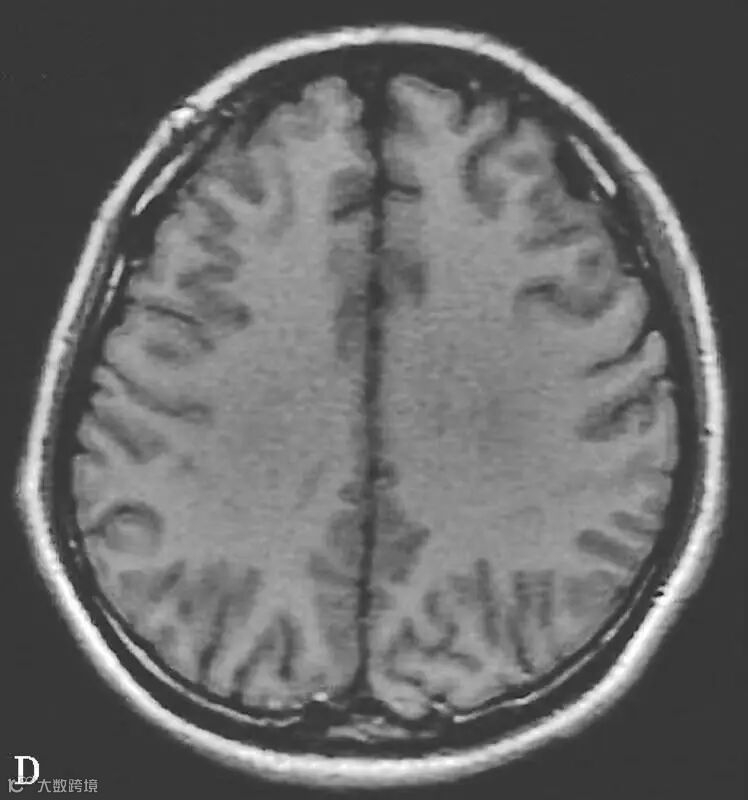

图6-11-2 弥漫性轴索损伤

男,36岁,外伤后2天。A~J(A、B.T2WI,C、D.T1WI,E、F.T2WI-FLAIR,G、H.DWI,I、J.ADC图):双侧额叶、半卵圆中心及胼胝体压部可见多发斑点状等T1稍长T2信号,边缘不清,FLAIR及DWI呈高信号,ADC图病灶信号减低 。